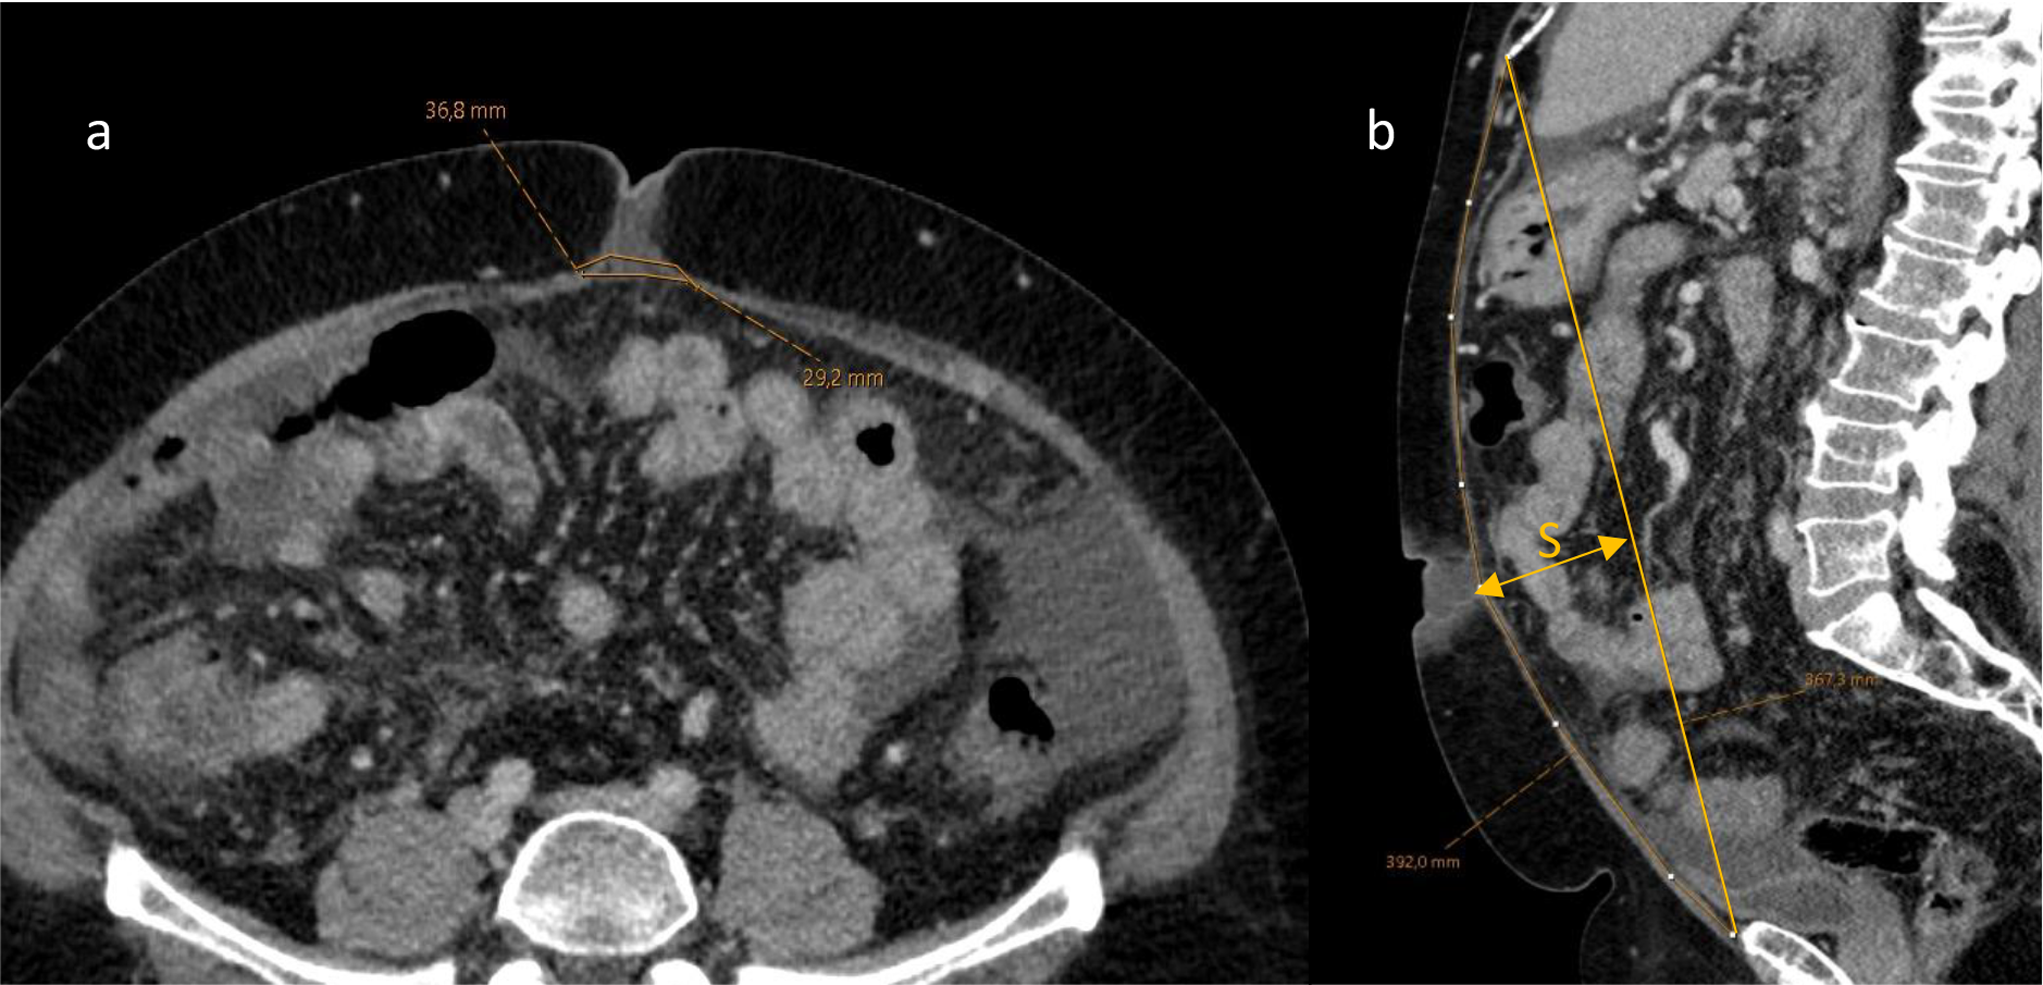

Fig. 1

Contrast enhanced CT scan in axial (a) and sagittal (b) slices with annotations measuring the linea alba width and the length of linea alba. In (c) we have highlighted the two lines required for the reconstruction and measurements of the sagitta (S; arrowed line.)

Patients with complete datasets were analyzed using the methods of Geroult et al. [10]. Briefly, the linea alba was visualized in the 3D viewer and distance measurements were performed at predefined locations: total distance of linea alba, sagitta of the linea alba and width measures at six different points along the linea alba as well as the maximal inter rectus distance.